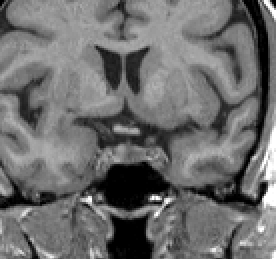

The Intracranial Cavity includes the whole brain volume (all brainstem, infundibular and pituitary, cerebellar, subcortical, and cerebral parenchyma) and total intracranial CSF (all CSF in ventricular and subarachnoid spaces).

Before beginning, brighten the scan to a degree where you can distinguish CSF from similarly colored bone or dura.

When segmenting, make frequent reference to other views to determine if an area is CSF or not.

Turn the automatically generated outline into a contour by un-extracting it with 'W'. Then draw 'd' and erase 'q' to make any necessary corrections, and finally save the outline. The basic idea is to obtain an outline that includes all CSF and excludes bone. Compact bone is very dark but the marrow inside the bone will be anywhere from gray to very bright.